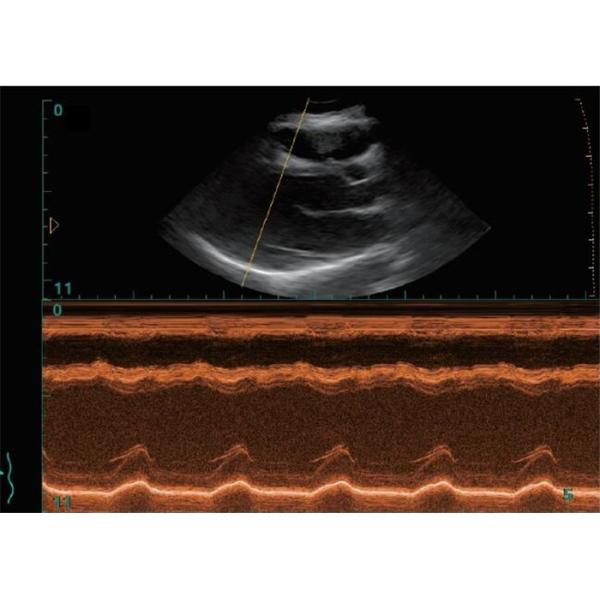

12 Inch Notebook Portable Ultrasound Scanner With Window 10 system(PC)

BIO 3000J is an advanced full-digital ultrasound technology system, with unique and perfect design .

The system brings high-definition images and at the same time greatly enhance the lightweight characteristics.

It provides totally new operation and clinical diagnostic experience to sonographer in daily working .

The B/W ultrasound scanner is equipped with multiple transducers, comprehensive functions and high mobility,

which makes it applicable to different body scans and clinic application.

12 Inch Notebook Portable Ultrasound Scanner With Window 10 system(PC) Images |